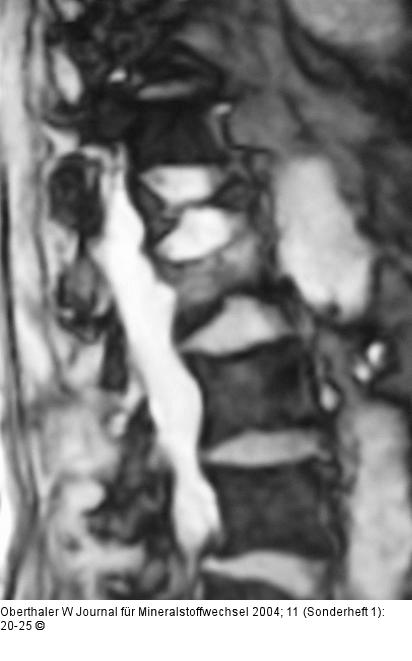

Abbildung 7: Kyphoplastie Typischer MRI-Befund einer älteren keilförmigen Kompressionsfraktur und eines frischen Einbruches ohne größere Deformität |

Typischer MRI-Befund einer älteren keilförmigen Kompressionsfraktur und eines frischen Einbruches ohne größere Deformität |